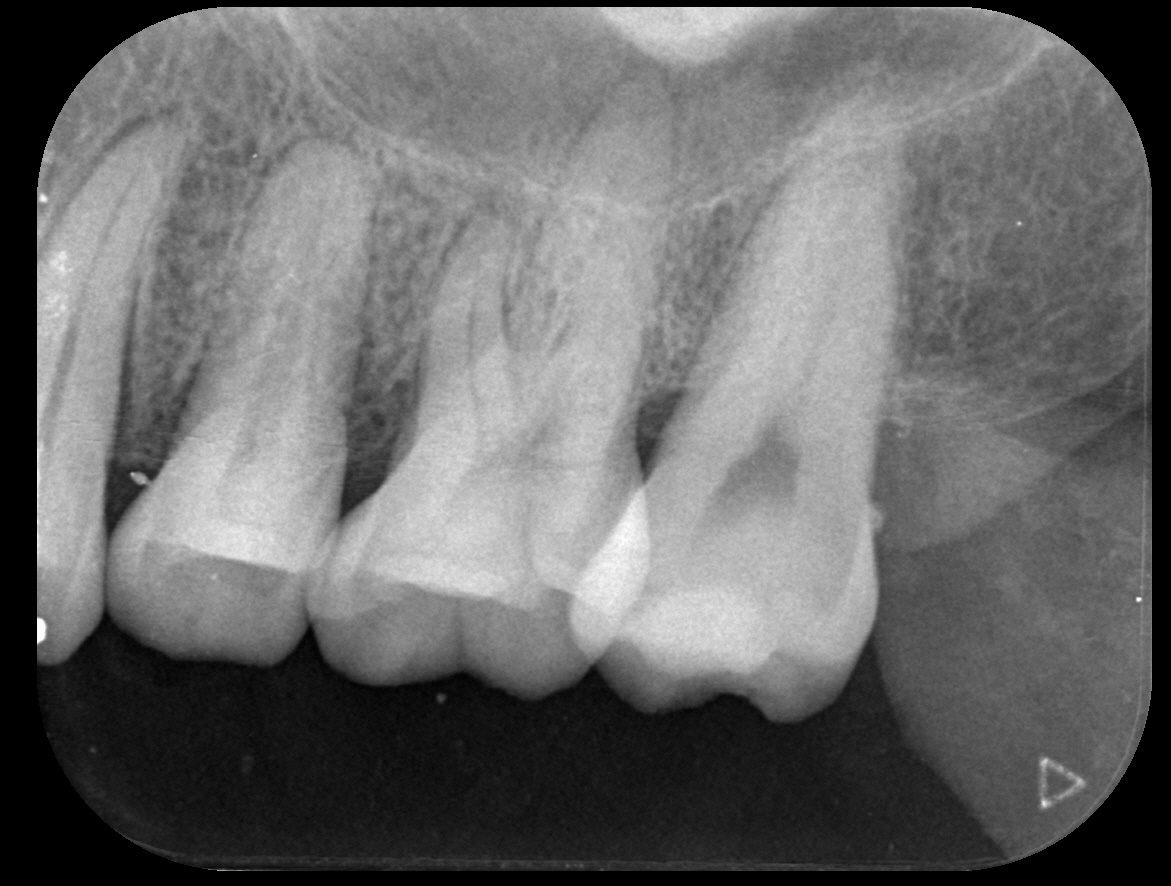

결과로 증명하는

치료케이스

상담부터 사후관리까지

환자 한 분, 한 분의 상태에맞춰 꼼꼼하게 진행합니다.

일반진료

BEFORE & AFTER